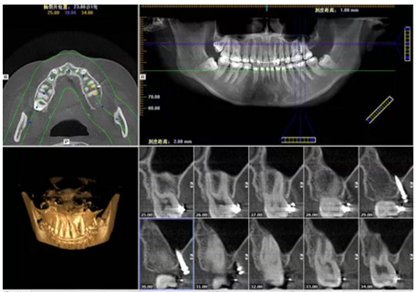

目前CBCT 廣泛應(yīng)用在口腔種植術(shù)前診斷與設(shè)計(jì)、口腔頜面部骨折和腫瘤、牙周疾病、顳下頜關(guān)節(jié)疾病、牙體牙髓疾病等領(lǐng)域,很大程度上取代了傳統(tǒng)的放射線檢查技術(shù)。CBCT 將掃描的頜骨影像數(shù)據(jù)導(dǎo)入相應(yīng)軟件中進(jìn)行三維重建,并進(jìn)行準(zhǔn)確測(cè)量,從而可以全方位的進(jìn)行手術(shù)模擬,進(jìn)而合理設(shè)計(jì)種植體的型號(hào)尺寸,同時(shí)可以觀測(cè)種植體與上頜竇及下牙槽神經(jīng)管之間的距離,并且可以對(duì)頜骨骨量骨質(zhì)進(jìn)行評(píng)估,以及模擬未來修復(fù)體與鄰牙對(duì)頜牙的位置關(guān)系等。

接下來,應(yīng)用口腔種植計(jì)算機(jī)設(shè)計(jì)軟件進(jìn)行三維計(jì)算機(jī)輔助手術(shù)規(guī)劃,利用這些軟件仿真手術(shù)模擬放置種植體,檢查植入方向,未來義齒修復(fù)體的修復(fù)空間以及牙鄰牙的關(guān)系。將這些信息參數(shù)轉(zhuǎn)化STL文件格式,通過數(shù)控機(jī)床或用快速成型方法加工,最終完成數(shù)字化導(dǎo)板的制作;數(shù)字化外科導(dǎo)板作為信息載體,將種植思路通過導(dǎo)板轉(zhuǎn)移到了手術(shù)過程中。